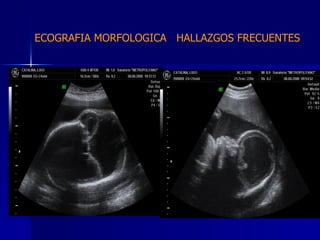

DTFRC-2007 ECOGRAFIA MORFOLOGICA  HALLAZGOS FRECUENTES   SISTEMA NERVIOSO CENTRAL TOTAL  8  26 % 1 HIDROCEFALIA 2 VENTRICULO MEGALIA 4 QUISTE DE PLEXO COROIDEO 1 ANENCEFALIA

ECOGRAFIA MORFOLOGICA  HALLAZGOS FRECUENTES